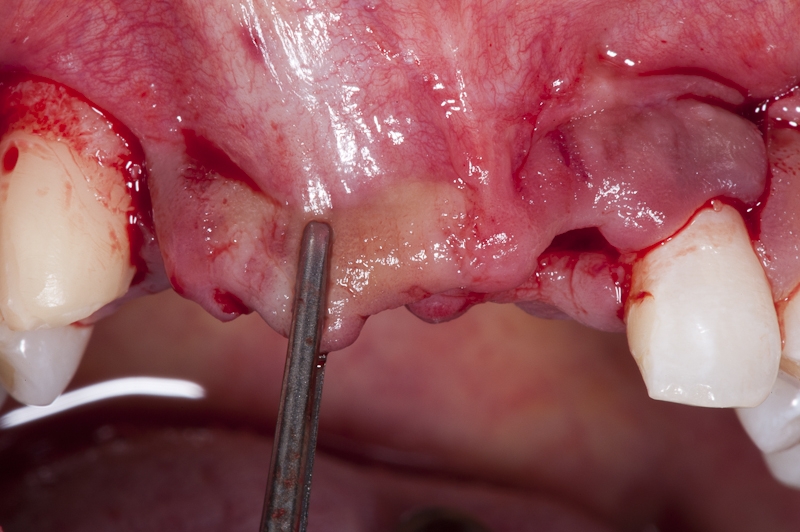

05/17 - Mobilisation of full flap is achieved by periostium incision in the bottom of the flap